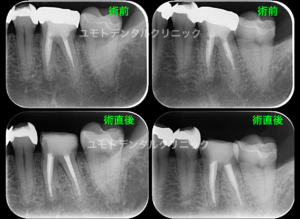

当院では根管治療のご依頼を頂いた際に根管充填後、原則として支台築造までを行わせていただいております。

通常(Pro root MTAなどのバイオセラミックで根管充填、パーフォレーションリペアと同時に根管充填を行う以外)は根管充填後、ラバーダム防湿下にて即時に直接法にて支台築造を行います。

1)ラバーダム防湿下でのより確実な接着操作

2)アポイント間の感染予防

3)間接法に比較し歯質削除量を最小限にできる

再感染防止、健全残存歯質の保存の観点から先生方のご理解をいただければ幸いです。